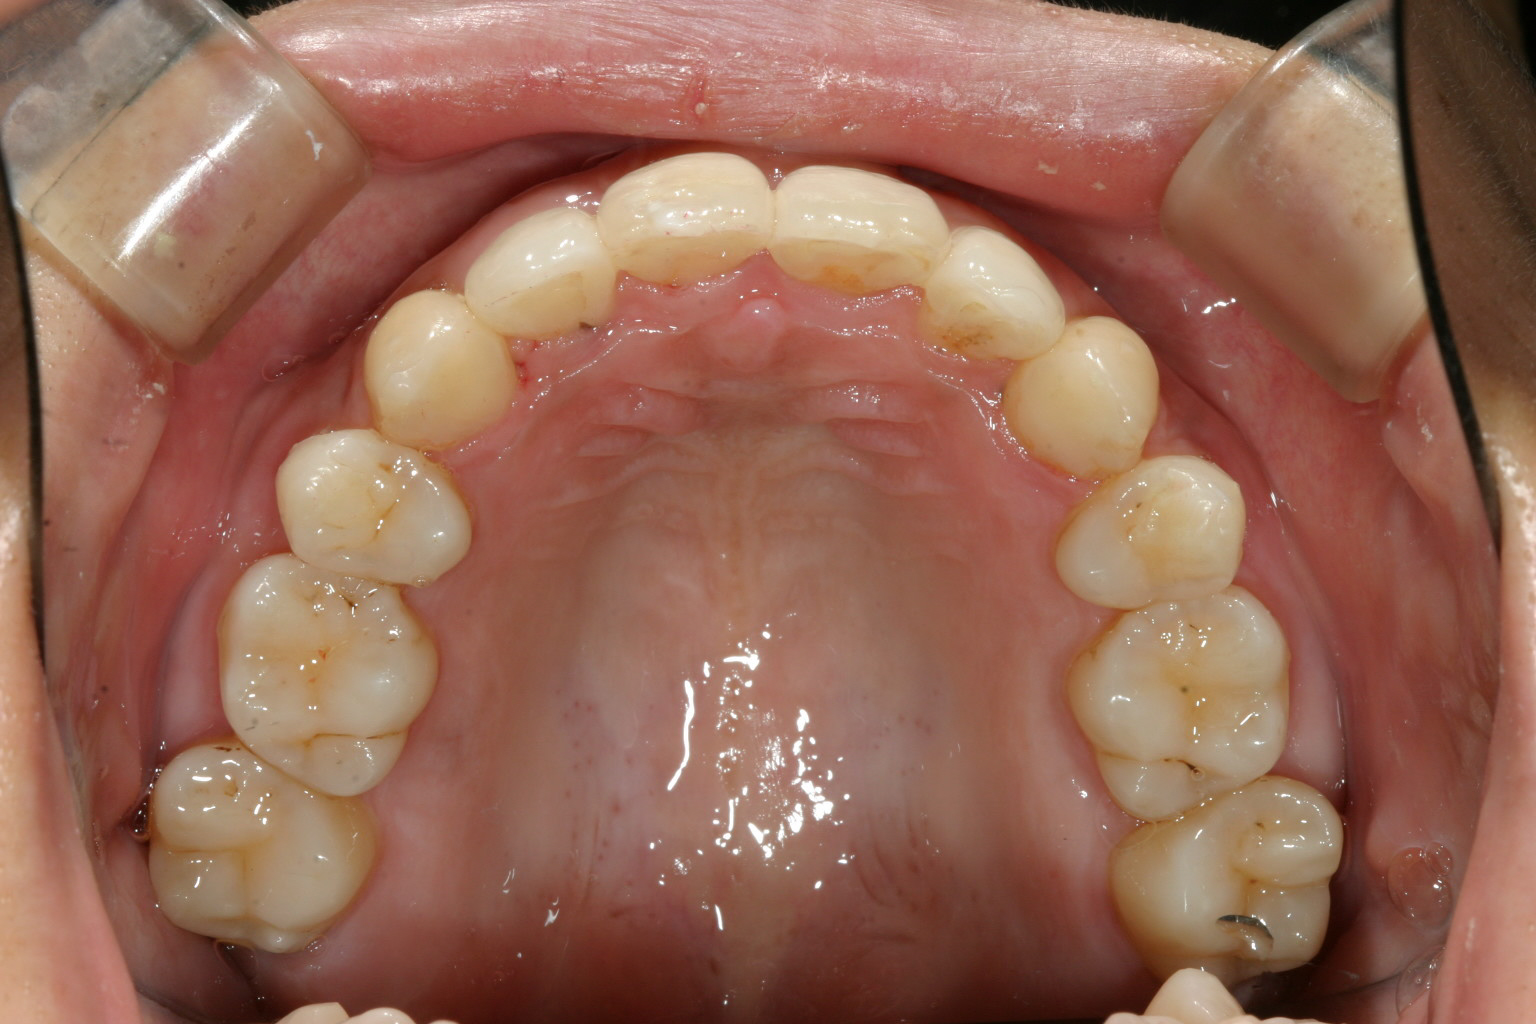

両側の八重歯が飛び出してますね!

左右の小臼歯を抜歯してその出来たスペースに八重歯を移動させました。

八重歯の突出が大きい為上下左右の小臼歯抜歯を選択しました。

それとアーチ幅の拡大も同時に行いました。